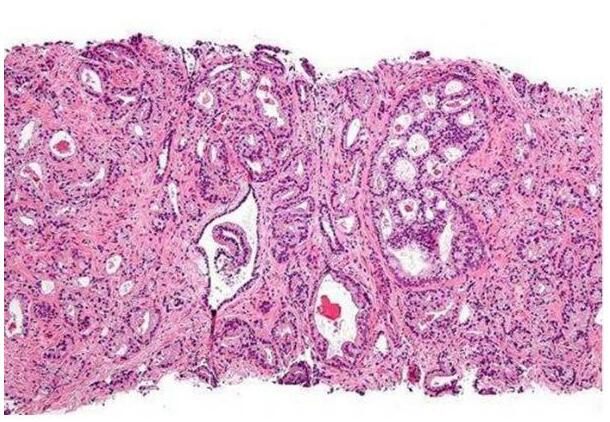

研究人员制备了一支针对Par6 345位丝氨酸磷酸化的特异性抗体,并通过体外实验对其特异性进行了验证。然后研究人员在正常的人类前列腺细胞和前列腺癌细胞中分别检测了内源性Par6的345位丝氨酸磷酸化水平。随后利用共聚焦显微镜技术观察了TGFβ处理的PC-3U前列腺癌细胞中磷酸化Par6的亚细胞定位。同时研究人员还对TGFβ处理的P3-3U细胞进行了侵袭实验,并通过免疫组化的方法分析了癌变的前列腺组织中磷酸化Par6的表达情况。